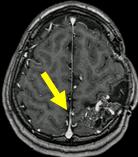

文字方塊: 每年磁共振造影追蹤動靜脈畸形可見逐年消失

文字方塊: 2006.02.21

文字方塊: 病患A 14歲 男性

診斷:動靜脈畸形